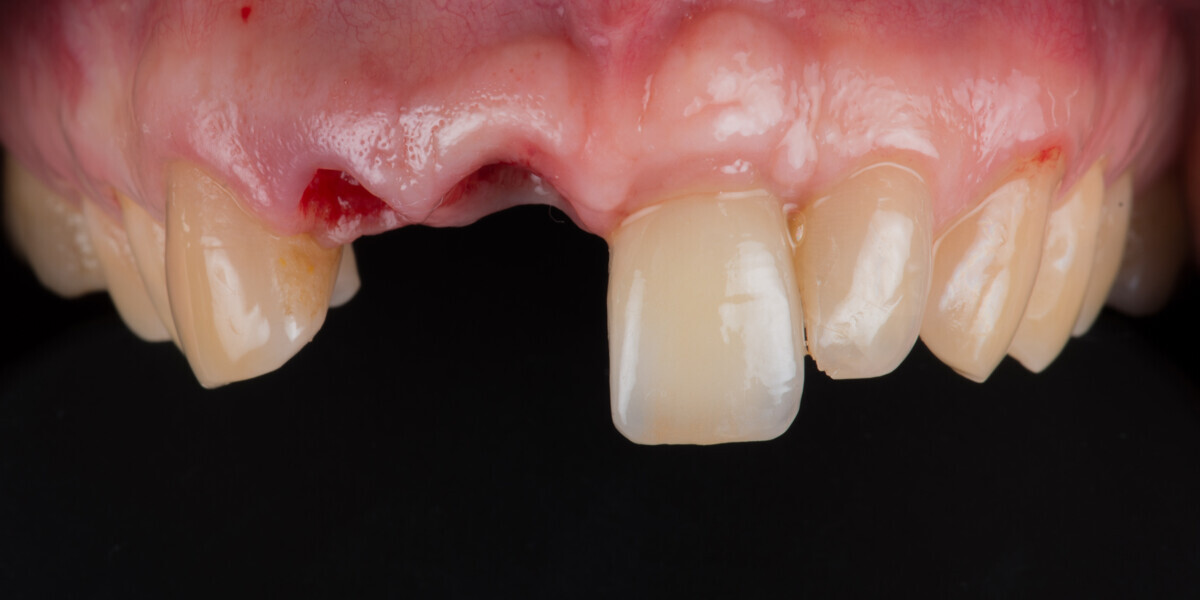

Immediate placement and restoration of a Straumann BLX implant replacing maxillary incisors